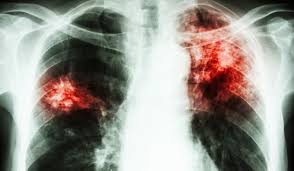

Iar ne situam pe primul loc in Uniunea Europeana, insa de aceasta data cu privire la numarul bolnavilor de tuberculoza. Aceasta afectiune se contracteaza cu usurinta si de aceea este dificil sa fie limitata in vreun fel. De asemenea Romania se afla printre premele locuri in Uniunea Europeana si in ceea ce priveste copiii cu tuberculoza.